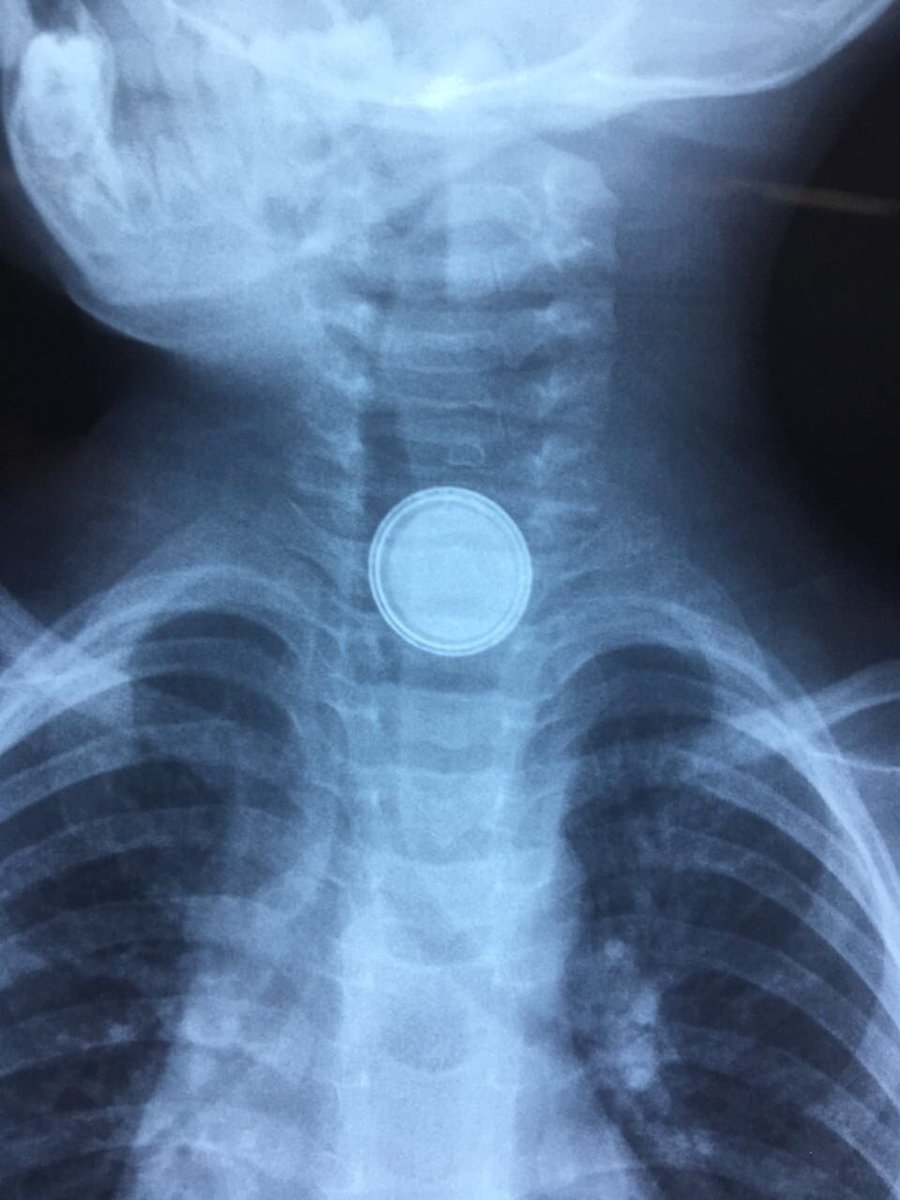

![]()

بطارية